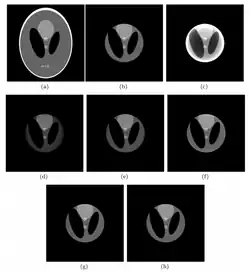

Eight views of an image

a) Shepp-Logan head phantom b) Crop of the phantom c) Reconstruction without extrapolation d) Reconstruction with constant, (e) quadratic and (f) mixed extrapolation